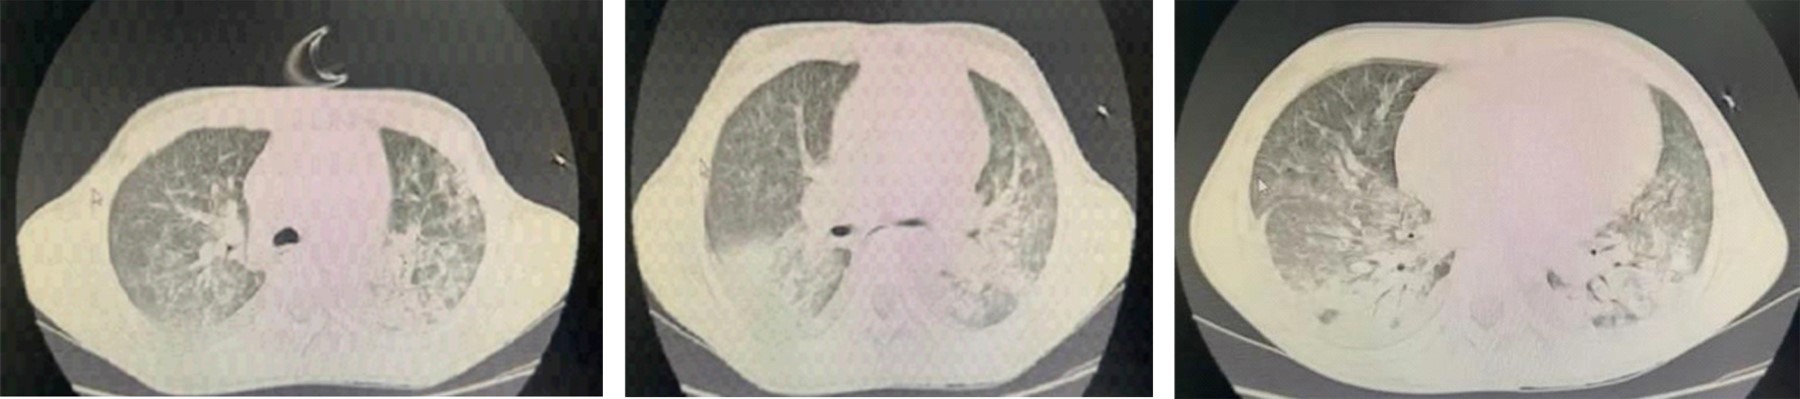

Figure 1